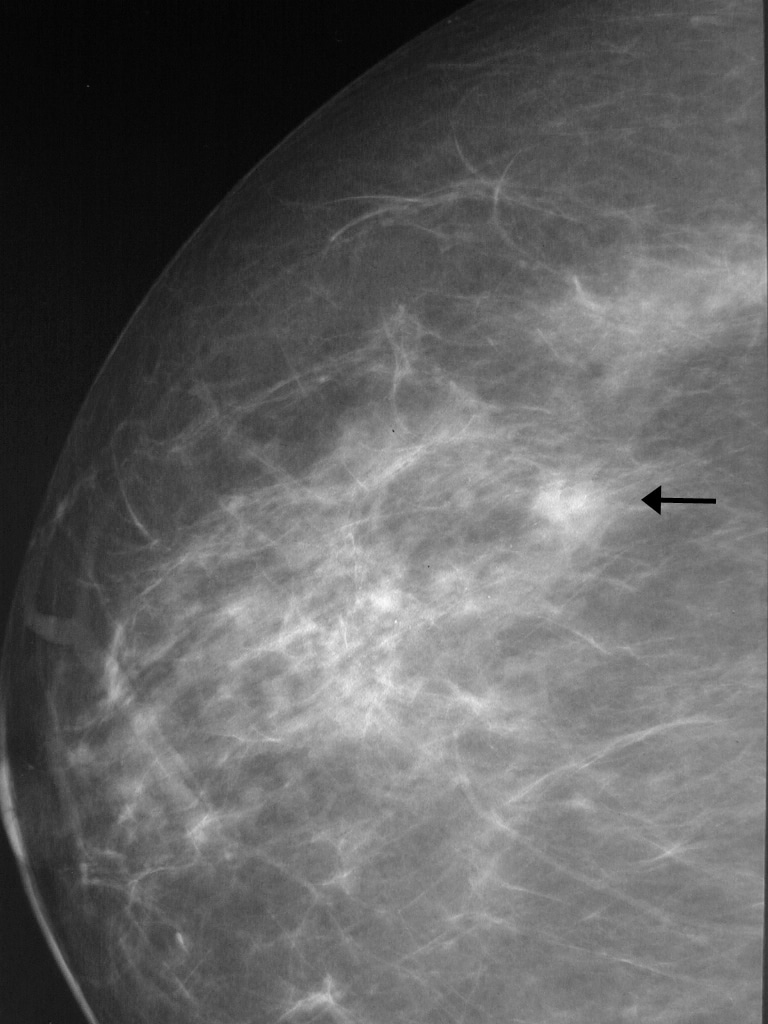

Что такое маммография: важность, процесс и результаты

Раздел: Необычные решения